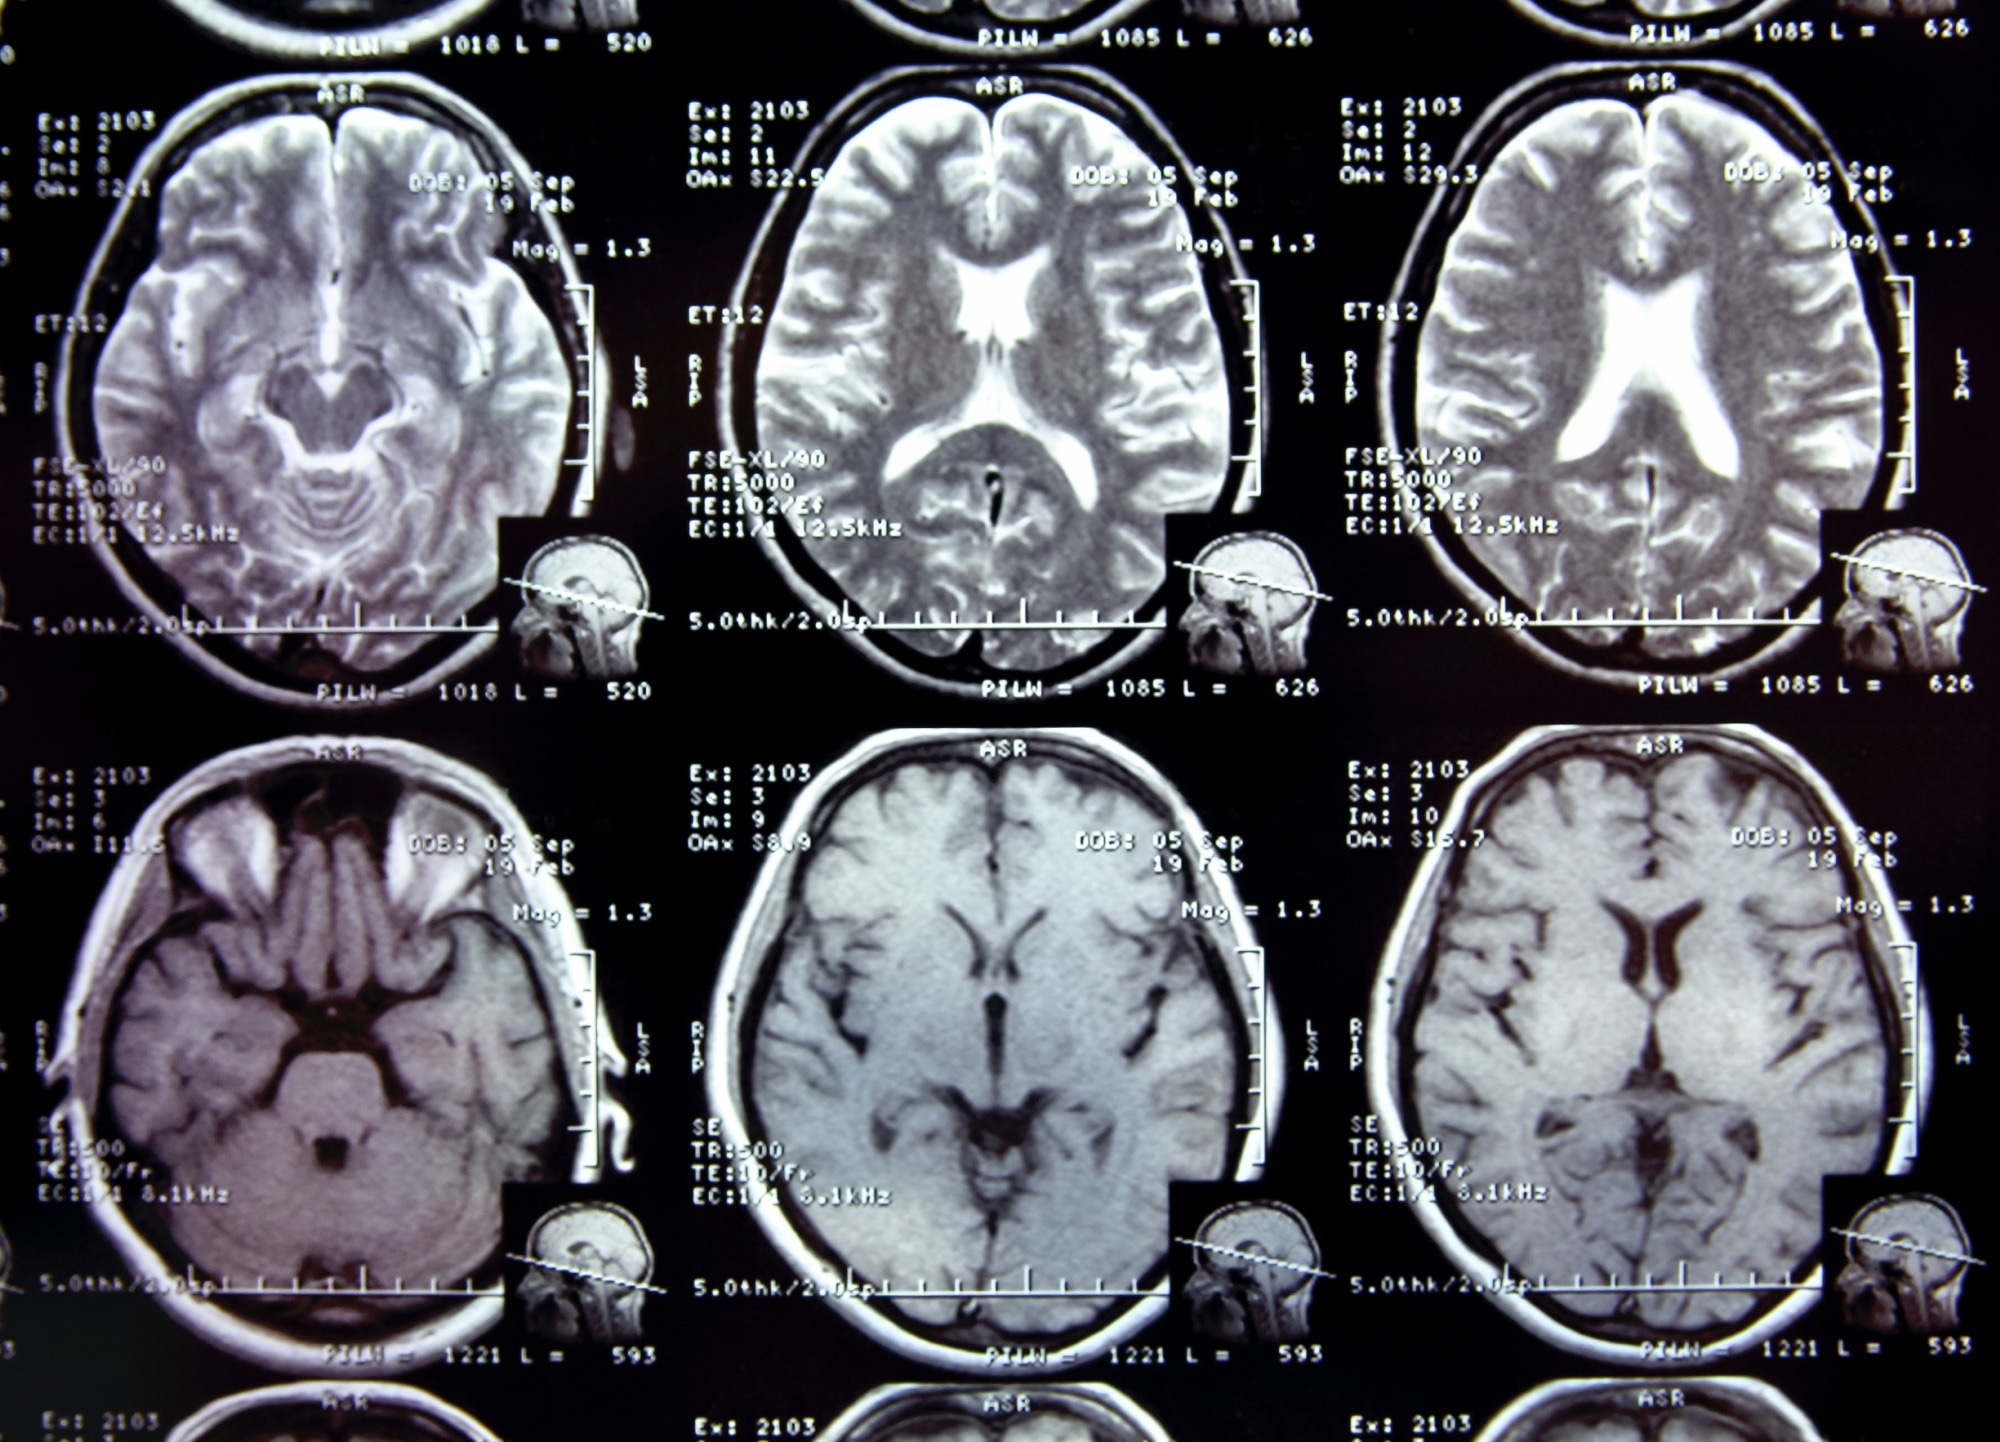

Study: COVID-19 and the impact on Alzheimer Study: COVID-19 and the impact on Alzheimer's disease pathology. Image Credit: alexialex / Shutterstock.com